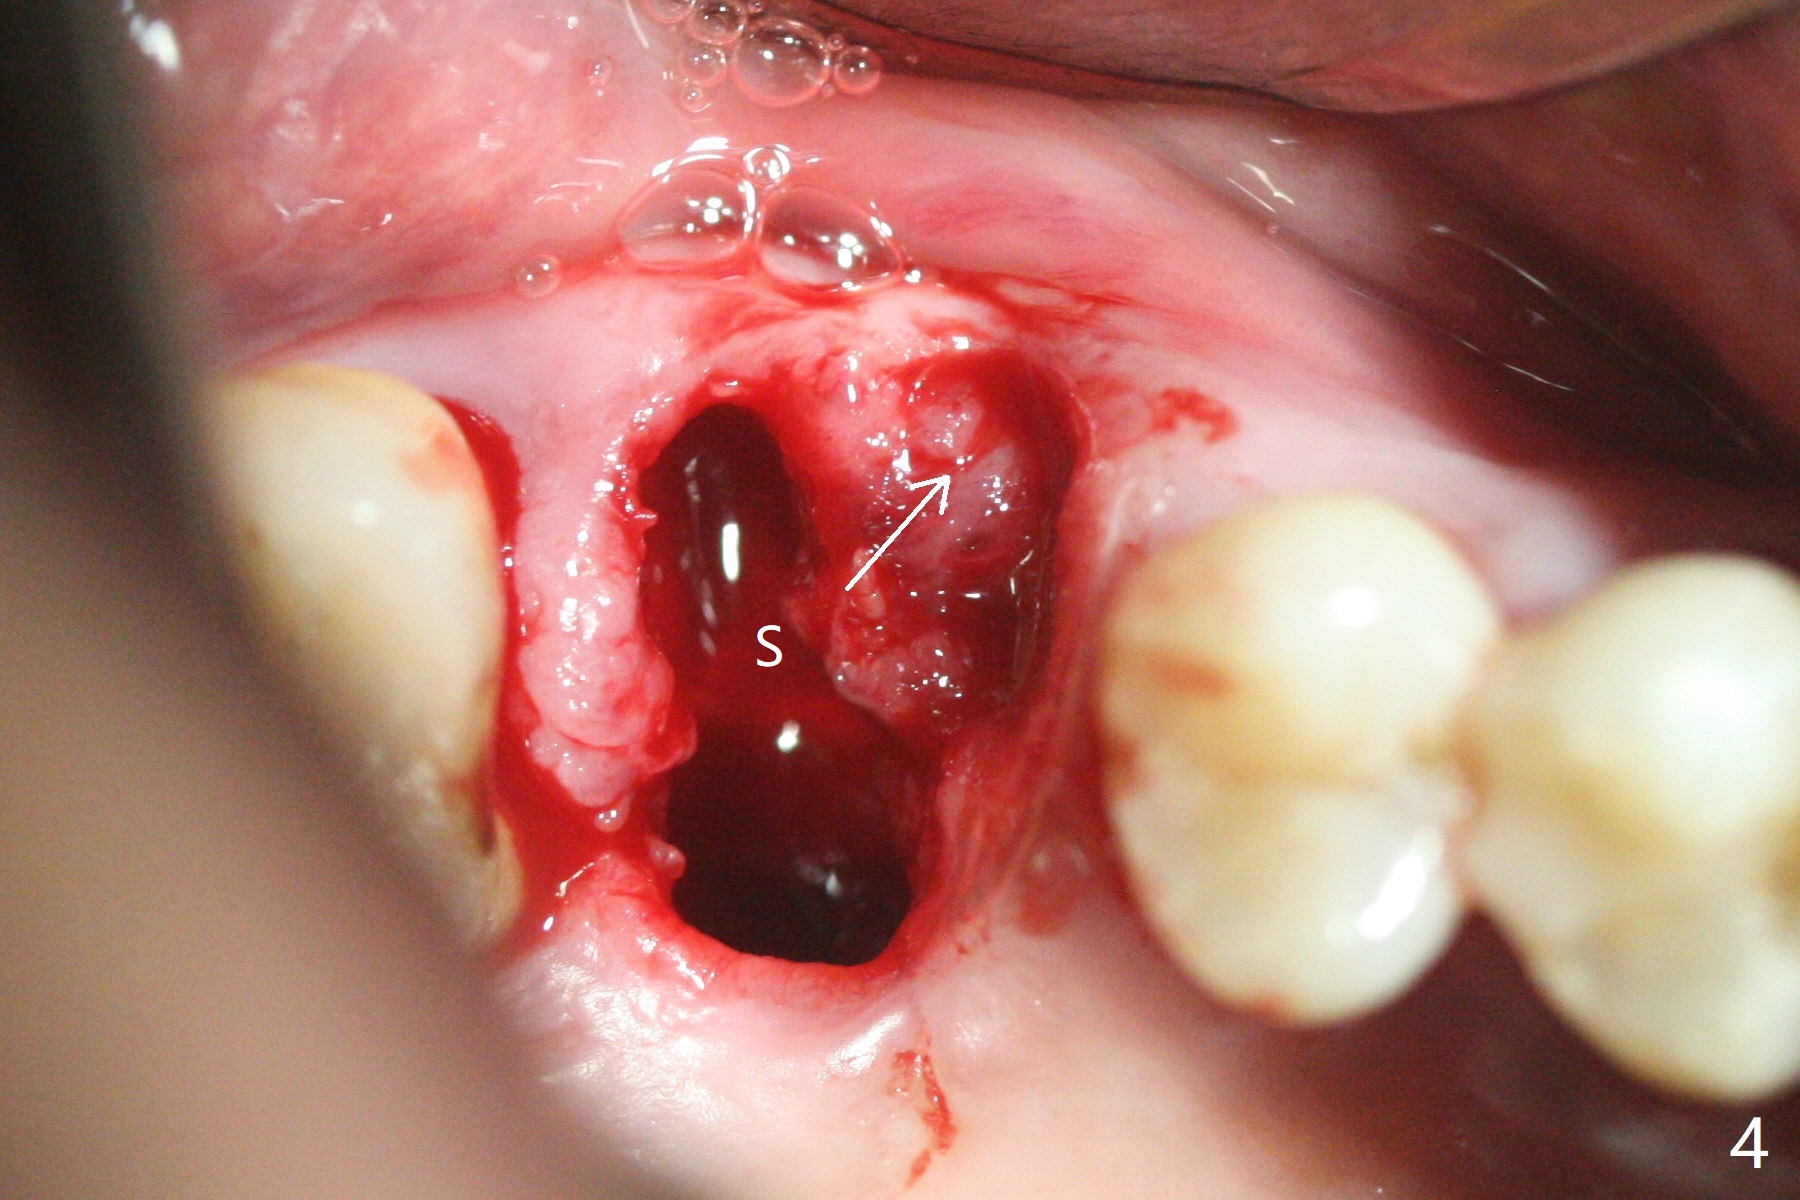

53岁男吸烟,牙周炎,咬合力大,3号牙颊侧(图一),腭侧(图二:P)牙龈退缩,尤其是近中颊侧根(图一:MB),拔牙后,中隔冠方(表面)有好像健康的牙龈(图三:*),近中,远中连接处切开(图三:虚线),将中隔牙龈推向近中颊侧牙槽窝(图四:箭头),修复退缩牙龈,而且暴露下面中隔(S),接着在它上面导板钻洞,避免软组织创伤。利用报废植体试图内提升(图五(红虚线:窦底)),最终正式植体完成提升(图六:黑*),初步在牙槽窝深部放置粘性骨粉(白*)后,放入基台,之后再次在植体,基台周围放置骨粉(图七:*),最后借助临时牙冠(图八,九:T)和外衬里(图八:R)封闭牙槽窝开口,G是近中颊侧迁移的牙龈。植体垂直进入上颌窦可以减少窦膜破裂(图五,六,九),术后没有鼻出血。术后1个月临时牙冠松动,去除牙冠和基台,安置愈合帽(图十)。表面骨粉遗失,但是颊侧移位的中隔牙龈好像帮助软组织预后。